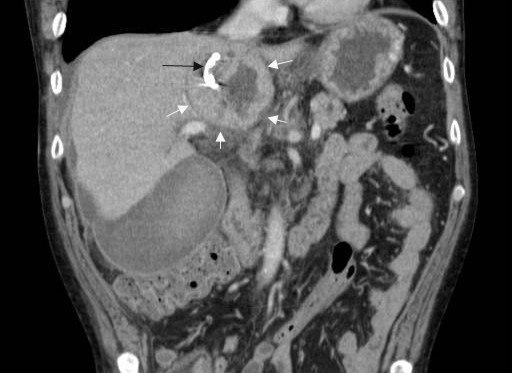

A 57-year-old man with a one year history of alcohol-induced chronic pancreatitis presented with a 1-month history of intermittent epigastric pain. He denied any associated nausea, vomiting, diarrhea, weight loss or other gastrointestinal symptoms. His past medical history was significant for hypertension, type 2 diabetes mellitus, dyslipidemia and chronic obstructive pulmonary disease. The abdomen was soft and non-tender. The liver and spleen were not felt, and no abdominal mass was appreciated. His physical examination was otherwise unremarkable. Laboratory evaluation revealed serum amylase of 356 U/L (reference range: 30-111 U/L) and a lipase of 679 U/L (reference range: 46-218 U/L). Complete blood counts, liver chemistries, carbohydrate antigen 19-9, and alpha-feto protein levels were all normal. Pancreas protocol CT scan of the abdomen revealed a 8x5 cm cystic fluid collection in the left liver lobe, an L-shaped subcapsular fluid collection inferior to right hepatic lobe 10x9 cm in size and a 2.4 cm complex fluid accumulation that involved the head and the superior aspect of the body of pancreas (Figure 1). CT guided diagnostic aspiration of the hepatic cystic lesion drained 100 mL of straw-colored fluid which showed no organisms on gram stain and was sterile on bacterial and fungal cultures. Cytological examination of the fluid did not reveal any malignant cells. The amylase level in this fluid was greater than 51,065 U/L which confirmed the diagnosis of intrahepatic pancreatic pseudocyst extension. At the time of CT guided aspiration, the pseudocyst was treated with percutaneous drainage with the placement of an 8F pig-tail catheter. The intrahepatic pancreatic pseudocyst extension failed to resolve even after 4 weeks of the pig-tail catheter placement (Figure 2). At this point, an ERCP was performed which revealed a normal cholangiogram. Pancreatography revealed a normal-appearing main pancreatic duct to the region of the pancreatic neck, and a ductal stenosis 12 mm in length was identified beginning at the pancreatic body near the neck. The main pancreatic duct and pancreatic duct branches were dilated upstream of the stenosis to about 7 mm (Figure 3). After performing an 8 mm ventral pancreatic sphincterotomy; the stricture was dilated with a 6 mm biliary dilating balloon and a 7F, 10 cm long pancreatic stent was inserted to the tail (Figure 4). Brush cytology and intraductal biopsy specimens were obtained from the stricture and revealed fibrosis and changes of chronic pancreatitis; they were negative for malignancy. EUS examination revealed a pancreatic head cystic lesion extending into the left hepatic lobe (Figure 5ab); fluid examination revealed an amylase of 54,450 U/L and the cytology was negative for malignancy. A follow-up pancreas protocol CT of the abdomen 6 weeks later revealed complete resolution of the pancreatic head fluid accumulation and the intrahepatic pancreatic pseudocyst and decrease in size of the L-shaped subcapsular fluid collection to 2x4 cm (Figure 6). Percutaneous drainage of the remaining L-shaped subcapsular fluid collection was discussed with the patient but he refused any percutaneous or surgical drainage. A follow-up pancreatogram revealed marked improvement in the pancreatic duct stricture. He remains asymptomatic after 9 months of follow-up.

Figure 2. CT scan at 4 weeks showing the persistent intrahepatic pseudocyst with pig-tail catheter in place. |